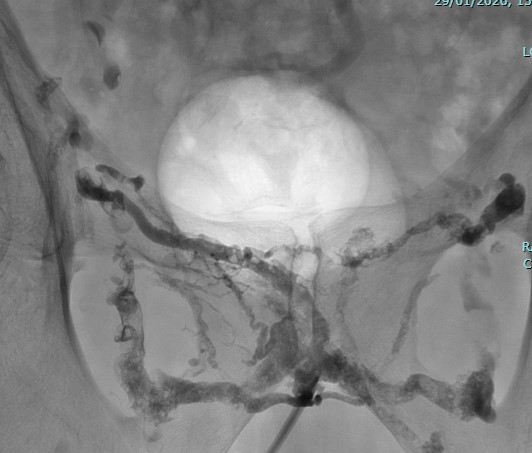

Angiographie de bilan par voie veineuse du petit bassin

Angiographie de contrôle après injection de Glubran et Lipiodol

Embolisation de celle-ci : de la colle biologique est injectée pour boucher la fuite.